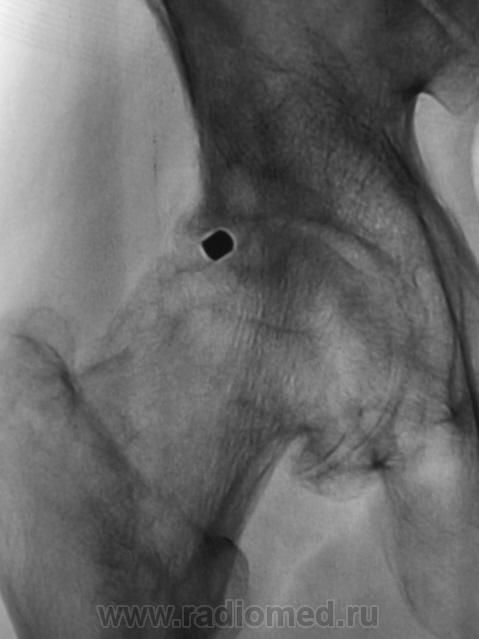

Почему-то на ум пришло сразу "Вот пуля пролетела ,и ага..".

это вероятно и есть состояние после огнестрельного ранения в виде ДОА 3 ст, инородное тело или нет?

Для точной локализации пули нужна попендикулярная ( как в "Двух капитанах" - палочки должны быть попендикулярны) проэкция. Может и не причина артроза?

КТ 2009 года.